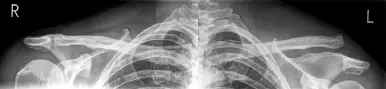

Abbildung: Schultereckgelenksprengung links, Typ Rockwood V mit Versatz des Schlüsselbeins um mehr als Schaftbreite